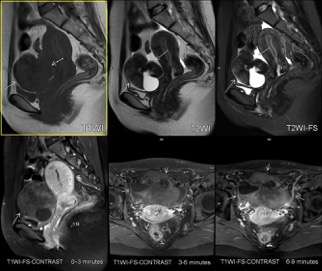

圖4 右側卵巢卵泡膜-纖維瘤組腫瘤 病變中纖維成份較為典型,呈T1WI等信號,T2WI低信號,增強掃描表現為漸進性中等延遲強化,邊界清楚,除實質成份外含均勻囊性成份。